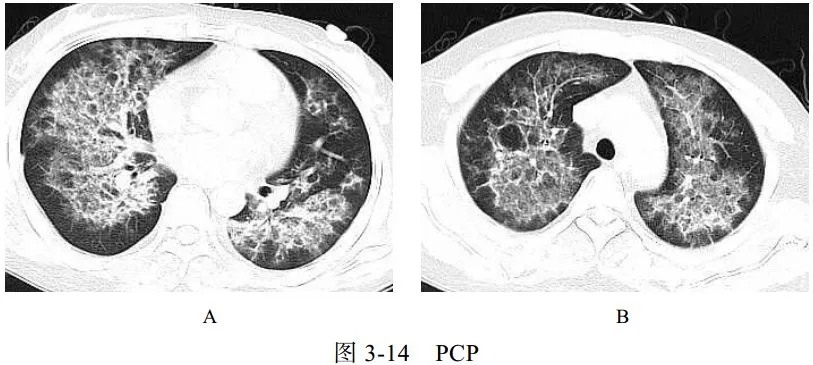

五、与肺孢子虫感染的鉴别诊断

卡氏肺孢子虫肺炎(PCP)是艾滋病患者最主要的机遇性感染之一。卡氏肺孢子虫引起Ⅰ型肺泡上皮细胞损害、Ⅱ型肺泡上皮细胞增生和间质性肺炎等病理改变,可导致肺间质性纤维化。临床表现为进行性呼吸困难、咳嗽、发热,病程持续数周或数月。PCP 相关检测查找卡氏肺孢子虫病原体。艾滋病患者免疫力极低,常合并其他感染,如结核、真菌等

影像学表现:

(1)广泛或局限性磨玻璃样密度影,以肺门周围为主,有融合趋势(图 3-14A)

(2)慢性及复发的病例可引起小叶间隔增厚及网格影

(3)可出现囊性病变(图 3-14B)、自发性气胸及肺实变影

(4)常不伴肺门及纵隔淋巴结肿大和胸腔积液